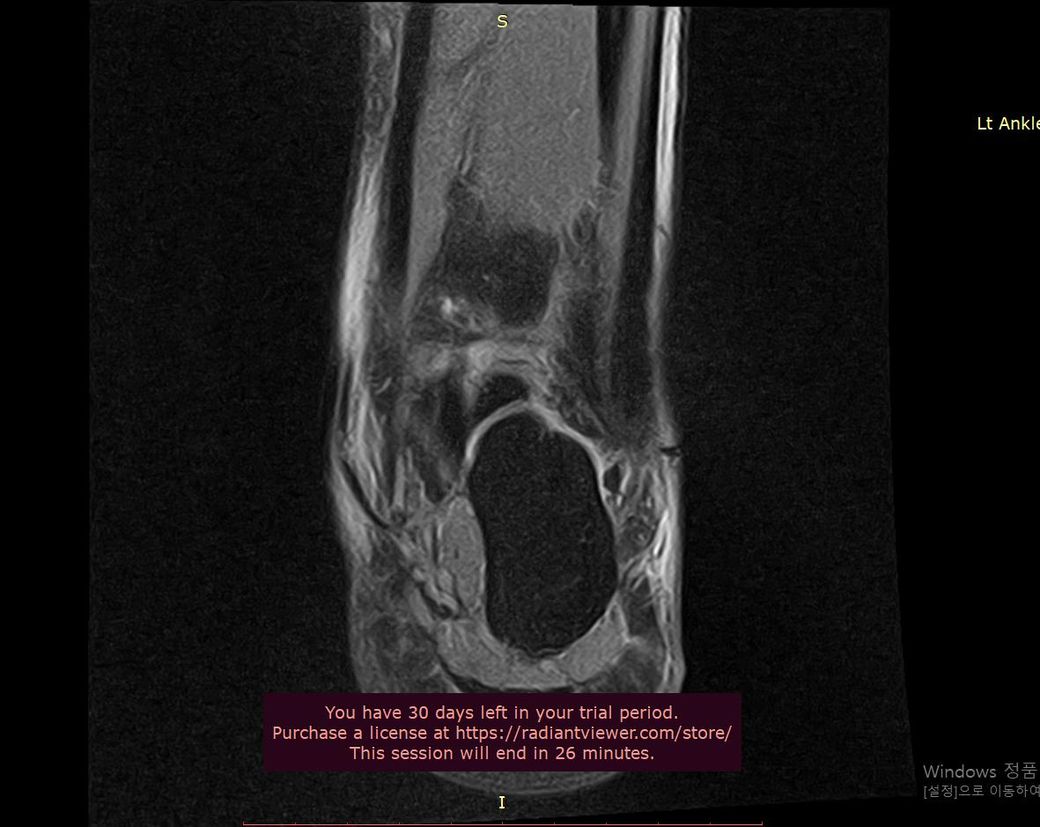

제가 발목 연골손상이라 mri와 내시경 사진이 있는데

어떤 상태인지 좀 다른 고견을 들어보고자 합니다

• 3번 째 사진

발목 연골 손상은 정도에 따라 회복 가능성 차이가 크고 mri와 내시경 소견이 매우 중요해요 완전 손상보단 부분 손상이면 재활과 치료로 걷기와 가벼운 운동은 충분히 가능할 수 있어요 이미지 확인은 병원에 내원 하셔서 정확한 진단을 받으시길 바랍니다!

현재 연골 손상이 있으신 것으로 보이는데요, 올려주신 사진이 참고에 도움이 될 수 있으나 정확한 소견을 말씀드리기에는 어려움이 있으므로 정확한 소견은 주치의에게 들어보시는 것이 좋겠습니다.